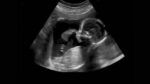

గర్భస్థ శిశువు ఆరోగ్యానికి రక్షణ కవచం ఆంధ్రప్రదేశ్ రాష్ట్ర చరిత్రలో తొలిసారిగా ఏడు ప్రభుత్వ ఆస్పత్రుల్లో TIFFA (Targeted Imaging for Fetal Anomalies) స్కానింగ్ యంత్రాలను ప్రభుత్వం అందుబాటులోకి తెచ్చింది. సాధారణంగా గర్భం దాల్చిన 18 నుండి 22 వారాల మధ్య ఈ స్కాన్ నిర్వహిస్తారు. దీనిని ‘అనామలీ స్కాన్’ అని కూడా పిలుస్తారు. గర్భస్థ శిశువు యొక్క శారీరక ఎదుగుదల, మెదడు, గుండె, వెన్నెముక మరియు ఇతర అంతర్గత అవయవాలలో ఏవైనా లోపాలు ఉన్నాయా … Continue reading TIFFA Services : ప్రభుత్వ ఆస్పత్రుల్లో ఫ్రీగా TIFFA సేవలు – మంత్రి సత్యకుమార్